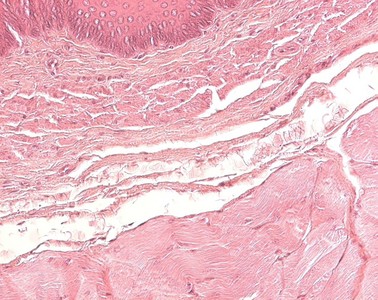

Präparat 3: Ösophagus (Mensch), Querschnitt, H.-E.

Lamina propria mucosae, Ösophagus

zwischen Lamina epithelialis und Lamina muscularis der Tunica mucosa gelegen, bildet die mittlere Schicht aus lockerem Bindegewebe, die besonders im unteren Ösophagusabschnitt ausgedehnte Venenplexus enthält. Die Lamina propria des Magens enthält die Magendrüsen und Zellen des Immunsystems sowie vereinzelt Lymphfollikel.

Lamina muscularis mucosae, Ösophagus

dritte Schicht der Tunica mucosa, die die Grenze zur Tela submucosa darstellt. Von hier aus können einzelne oder Bündel glatter Muskelzellen in das Schleimhautbindegewebe einstrahlen und so das Relief der Magenoberfläche verändern

An die Lamina propria mucosae schließt sich die Lamina muscularis mucosae aus glatter Muskulatur an. Nach außen folgt die Tela submucosa (oder einfach nur "Submukosa" genannt). Diese stellt eine Verschiebeschicht aus lockerem Bindegewebe dar. In ihr findet man Lymphozyten, Blutgefäße (Kapillaren, Venolen, Arteriolen), Nerven (Plexus submucosus) und die Glandulae oesophageae, die ein muköses Sekret absondern.